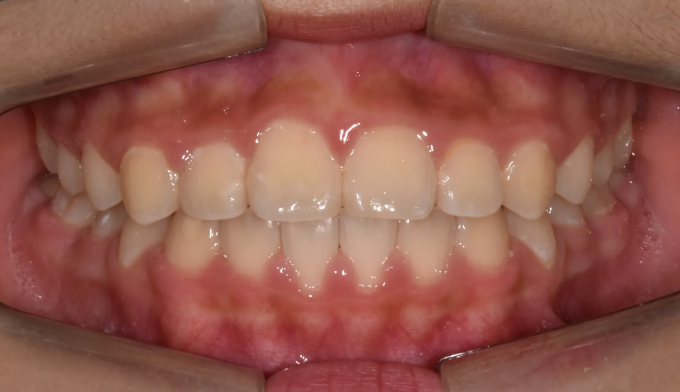

안모상으로는 반대교합도, 주걱턱도 심해보이지 않습니다.

하지만 엑스레이 검사시 주걱턱 경향이 심한 경우로 성장조절을 시작하였습니다.

1차교정 후 영구치가 다 나올때까지 지켜본 결과 1차교정으로 인해 보다 더 자연스러운 안모를 가지게 되었다고 생각합니다. 위턱이 아래턱 안에 갇혀있게 된다면 중안면부위의 결핍이 주걱턱 경향을 더 심하게 만들 가능성이 높기 때문입니다.